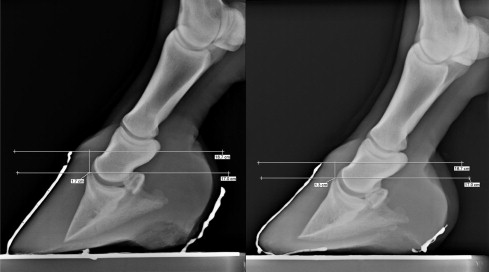

Understanding "Sinkers"and Hoof Capsule Rotation (#1 0f 2)

Reversing Hoof Capsule Rotation and Distal Descent/ Sinking (#2 of 2) 2022 prenstation for PHCP

P3 and P2 Development

Auburn Study: Caudal Foot Evaluation

Predictive modeling of the equine heel

Recently it has been proposed that healthy soft tissue structures of the equine heel play a primary role in equine soundness. Historically, little attention has been given to the significance of the health of the equine heel soft tissue structures, which are uniquely positioned so as to provide support and protection to the navicular apparatus. More